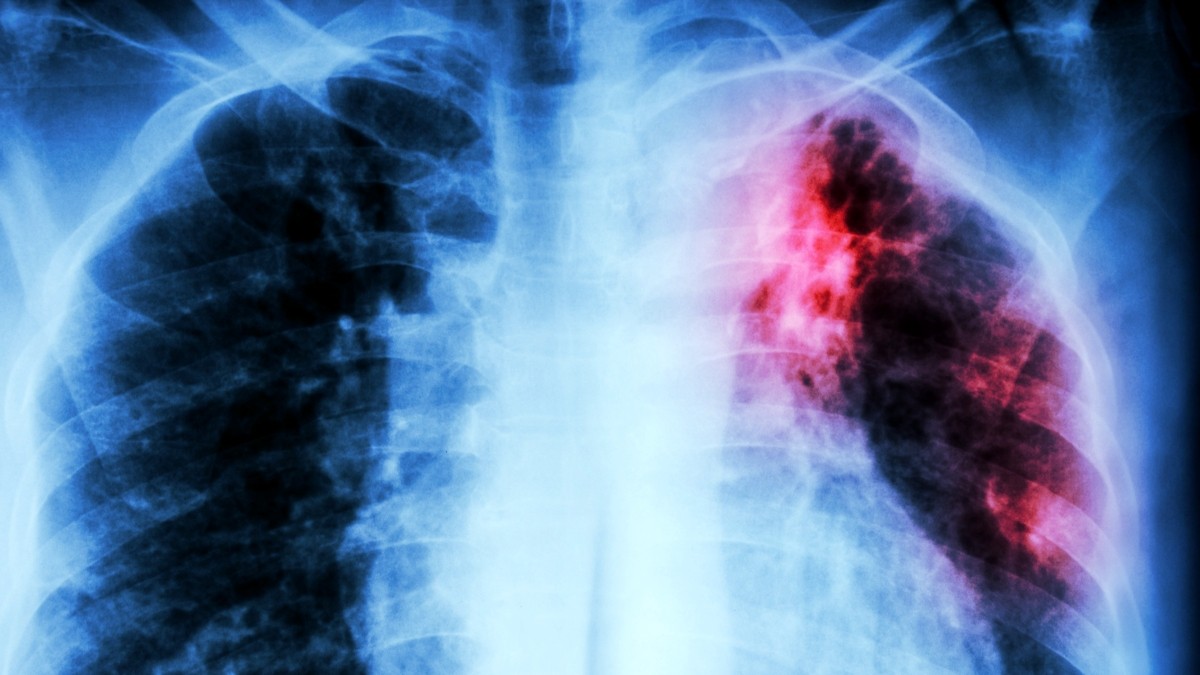

Туберкульоз (ТБ), захворювання, яке колись вважалося відступаючим, знову набирає обертів у всьому світі і все частіше стає стійким до існуючих антибіотиків. Всесвітня організація охорони здоров’я (ВООЗ) визнає це критичною кризою громадської охорони здоров’я, але нещодавні дослідження вселяють нову надію у боротьбі із смертоносною інфекційною хворобою у світі.

Туберкульоз забирає понад мільйон життів щорічно і легко поширюється повітрям. Хоча він виліковний, ефективне лікування не завжди є доступним, а повний курс може займати місяці, що сприяє зростанню лікарсько-стійких штамів. Захворювання непропорційно сильно вражає вразливі групи населення, у своїй соціально-економічні чинники та сила імунної системи грають вирішальну роль виживання. Це також прихована загроза: за оцінками, чверть населення світу має латентну ТБ-інфекцію, яка може ніколи не перерости в активне захворювання.